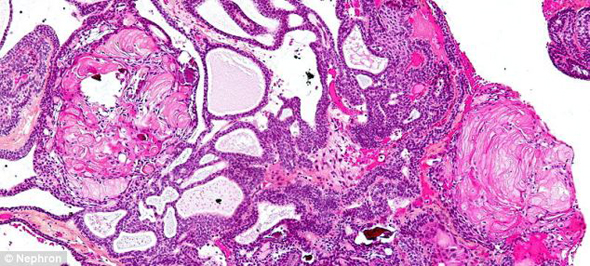

En el estudio, publicado, los investigadores sostienen que el tumor Craneofaringioma Adamantinomatosa (extirpado quirúrgicamente), surgió de la Bolsa de Rathke, precursor embrionario de una parte de la hipófisis. Esos tumores a veces están rellenos de líquido viscoso de color amarillo que contiene cristales de colesterol. Sin embargo, nunca antes se habían documentado casos con dientes dentro de ellos louis vuitton outlet